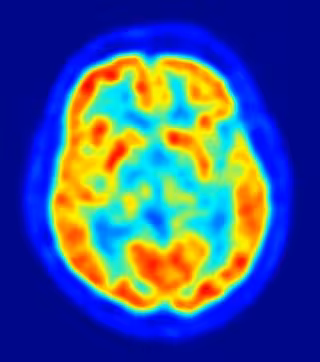

Los científicos saben desde hace bastante tiempo que se generan nuevas células cerebrales continuamente en regiones específicas del cerebro después del nacimiento. Este proceso, denominado neurogénesis, ocurre en una proporción significativamente mayor durante la infancia y la adolescencia que en la edad adulta, sin embargo, la mayoría de las investigaciones se habían centrado, hasta ahora, en la función de estas neuronas en cerebros más viejos.

Curiosamente, los esquizofrénicos tienen un déficit en la generación de nuevas neuronas en el hipocampo, una de las áreas del cerebro donde se crean nuevas neuronas. Dado que los síntomas de la esquizofrenia surgen por primera vez en la adolescencia, es posible que el déficit en la generación de nuevas neuronas durante este periodo, o incluso en la infancia, aporte nuevas pistas sobre el desarrollo de algunos déficits sociales y cognitivos observados en esta enfermedad.